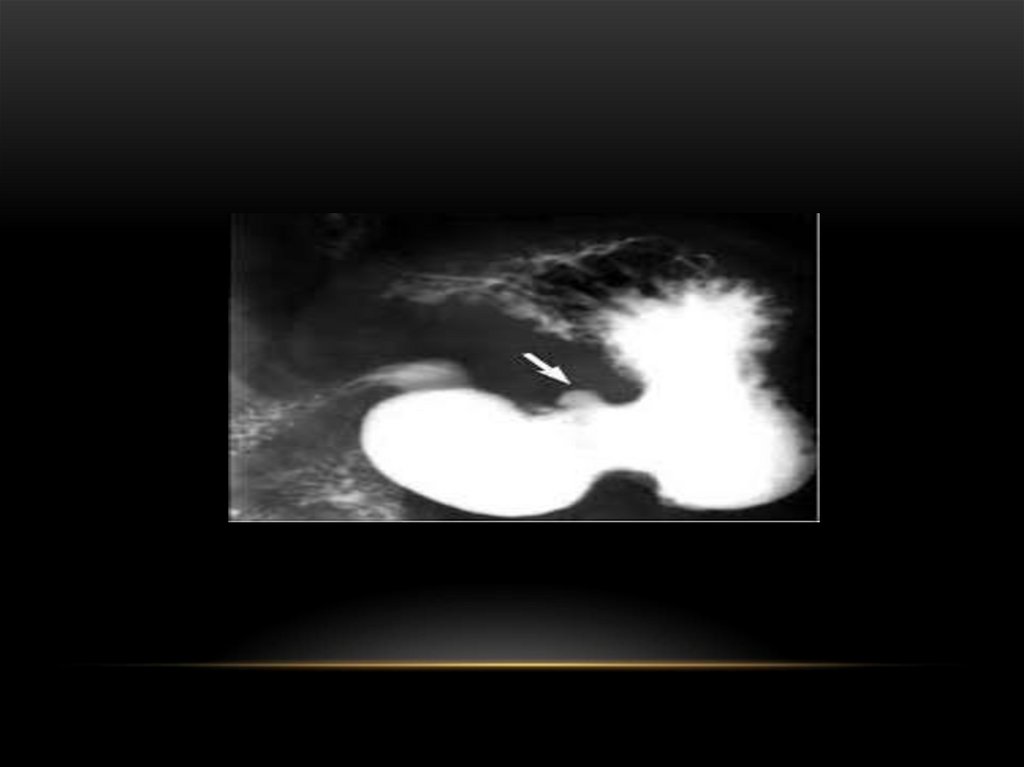

АСҚАЗАННЫҢ ОЙЫҚ ЖАРА АУРУЫ

Асқазан шырышты қабаты дефекті